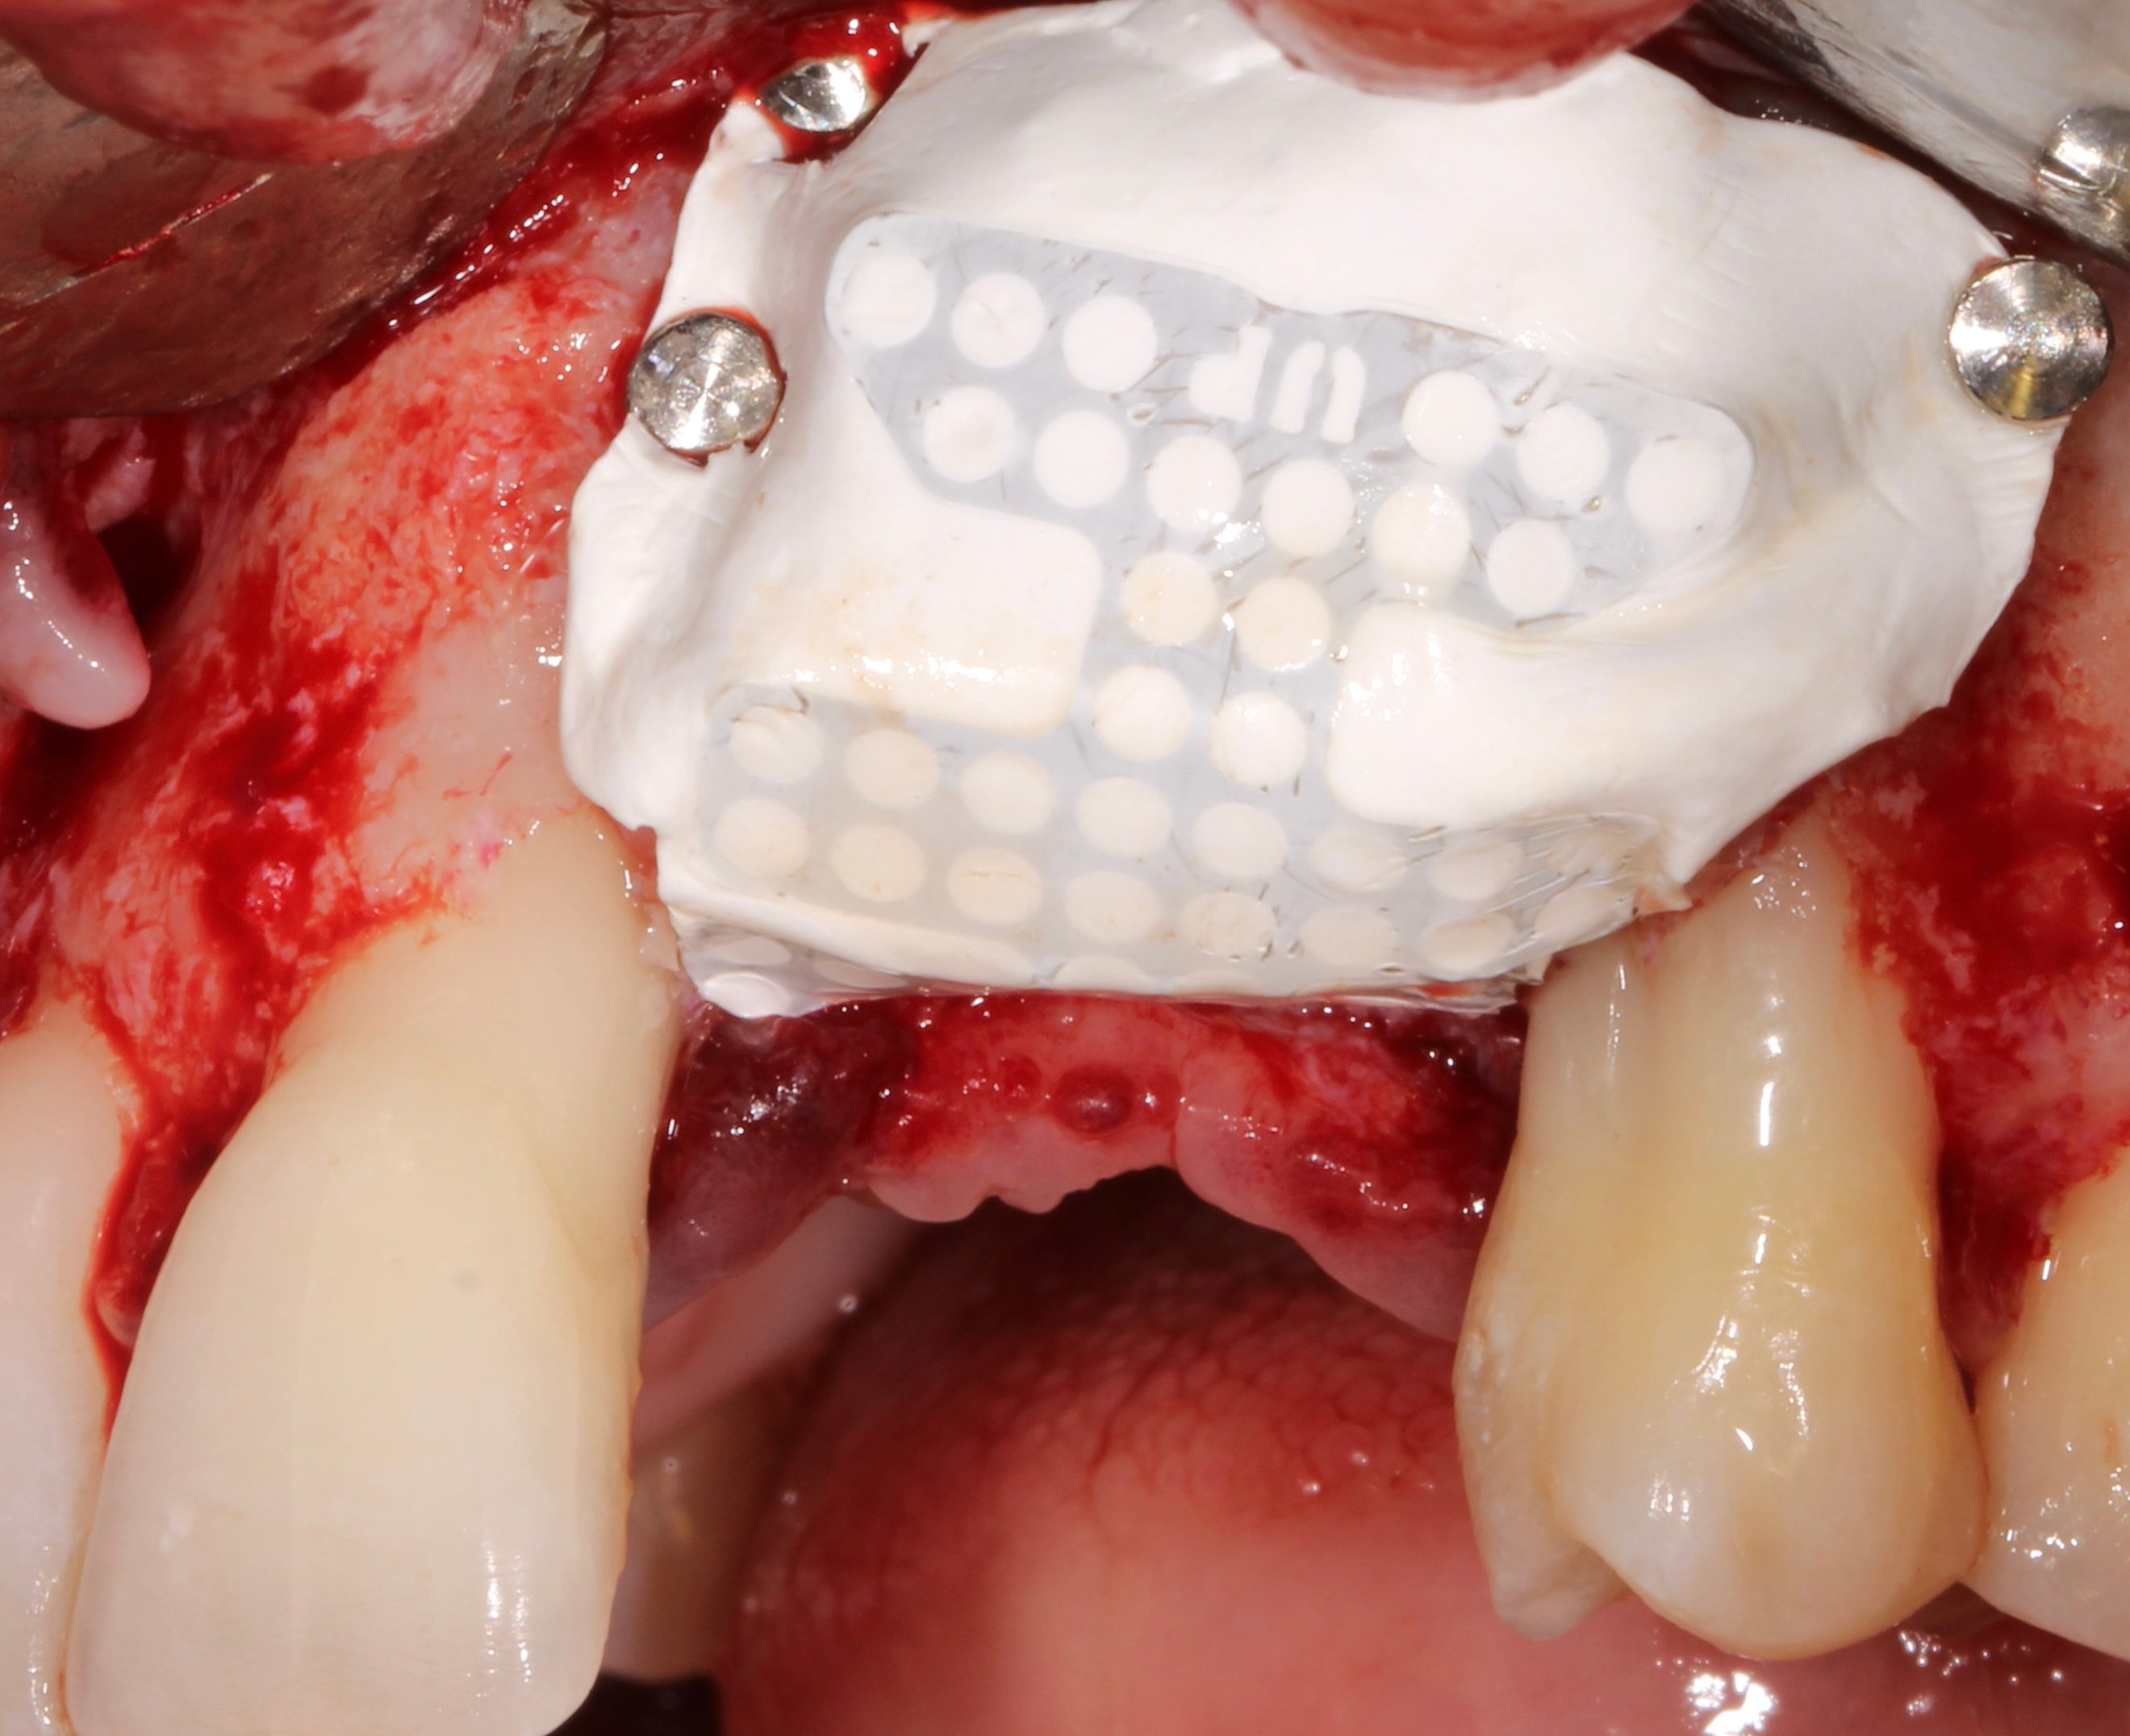

- 3 months later: (which turned out to be 2 years later because the patients was treated and failed elsewhere): 3D guided bone regeneration using 100% autogenous bone and a PTFE, Ti-reinforced NeoGen® membrane which was fixed by Neoss Tacks.

1 NeoGen Ti-Reinforced PTFE Membrane.